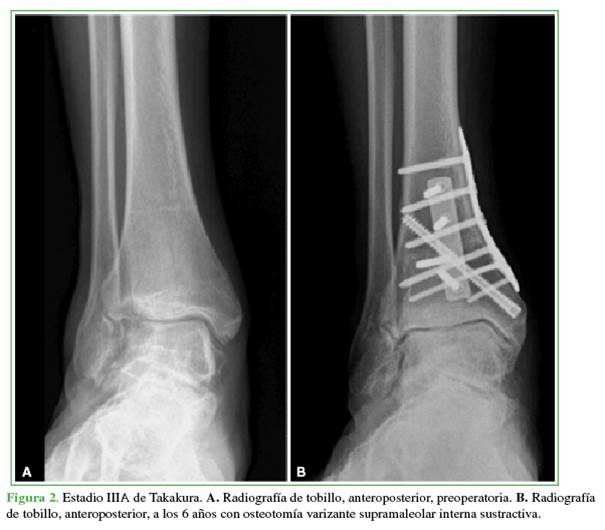

La artrosis se clasificó según la clasificación de Takakura-Anaka en la radiografía de frente con apoyo. Esta clasificación incluye cuatro estadios; I: no hay disminución del espacio articular, pero hay esclerosis subcondral del hueso y osteofitos; II: disminución del espacio articular medial o lateral; IIIA: obliteración del espacio medial o lateral; IIIB: obliteración del espacio medial o lateral que se extiende hasta el domo astragalino; IV: obliteración completa del espacio articular.18

Antes de la cirugía, seis (46,1%) practicaban actividad deportiva recreativa y todos ellos retornaron al deporte. En 12 (92,3%), se logró la consolidación radiográfica luego de la cirugía, en una mediana de 10.4 semanas (RIC 8-12) (Figuras 2 y 3). Se observó seudoartrosis en un paciente, por lo que requirió una cirugía de revisión. Se realizaron 25 procedimientos agregados (Tabla 2).